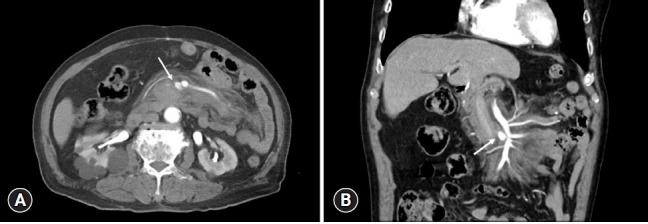

Mesenteric injury occurs rarely in cases associated with blunt abdominal trauma. Despite its low incidence, mesenteric injury can lead to fatal outcomes such as hypovolemic shock due to hemoperitoneum or sepsis due to intestinal ischemia, or perforation-related peritonitis. For mesenteric injuries, especially those involving massive bleeding, intestinal ischemia, and perforation, the standard treatment is surgery. However, in the case of operative management, it should be borne in mind that there is a possibility of complications and mortality during and after surgery. The usefulness of transcatheter arterial embolization (TAE) is well known in solid organs but is controversial for mesenteric injury. We present a 75-year-old man with mesenteric injury due to blunt abdominal trauma. Initial abdominal computed tomography showed no hemoperitoneum, but a mesenteric contusion and pseudoaneurysm with a diameter of 17 mm were observed near the origin of the superior mesenteric artery. Since there were no findings requiring emergency surgery such as free air or intestinal ischemia, it was decided to perform nonoperative management with TAE using microcoils in hybrid emergency room system. TAE was performed successfully, and there were no complications such as bleeding, bowel ischemia, or delayed bowel perforation. He was discharged on the 23rd day after admission with percutaneous catheter drainage for drainage of mesenteric hematoma. The authors believe that treatment with TAE for highly selected elderly patients with mesenteric injuries has the positive aspect of minimally invasive management, considering the burden of general anesthesia and the various avoidable intraoperative and postoperative complications.

肠系膜损伤在钝性腹部创伤相关病例中很少见。尽管其发病率较低,但肠系膜损伤可导致致命后果,如因腹腔积血引起的低血容量性休克,或因肠缺血引起的败血症,或穿孔相关的腹膜炎。对于肠系膜损伤,尤其是那些涉及大量出血、肠缺血和穿孔的损伤,标准治疗方法是手术。然而,在手术治疗的情况下,应牢记手术期间和术后存在并发症和死亡的可能性。经导管动脉栓塞术(TAE)在实体器官中的作用已广为人知,但在肠系膜损伤方面存在争议。我们报告一名75岁男性因钝性腹部创伤导致肠系膜损伤。最初的腹部计算机断层扫描显示没有腹腔积血,但在肠系膜上动脉起源附近观察到肠系膜挫伤和直径为17毫米的假性动脉瘤。由于没有发现需要紧急手术的情况,如游离气体或肠缺血,因此决定在混合急诊室系统中使用微线圈对该患者进行TAE非手术治疗。TAE手术成功,没有出现出血、肠缺血或延迟肠穿孔等并发症。患者在入院后第23天出院,采用经皮导管引流术引流肠系膜血肿。作者认为,考虑到全身麻醉的负担以及各种可避免的术中及术后并发症,对于经过严格筛选的老年肠系膜损伤患者,TAE治疗具有微创管理的积极意义。